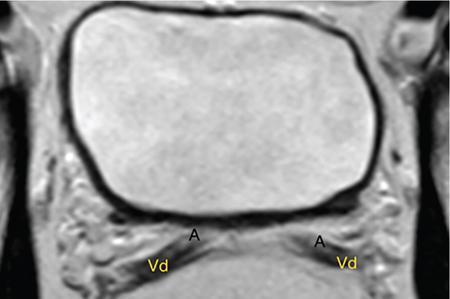

IMAGING ANATOMY OF MALE REPRODUCTIVE SYSTEM Ganesh Rajagopal The male reproductive system is formed by testes, ejaculatory ducts, seminal vesicles (SVs), prostate and penis. Various diagnostic imaging modalities like ultrasound (US), computed tomography (CT), magnetic resonance imaging (MRI) and positron emission tomography (PET) are helpful in the diagnostic evaluation of male reproductive system. Various indications for imaging may include acute scrotum (testicular torsion, trauma and epididymo-orchitis), scrotal swelling (hydrocele, spermatocele, idiopathic scrotal wall oedema and scrotal abscess) and infertility. US and MRI are the commonly used imaging modalities in male reproductive system which complement each other. CT is not very useful due to poor contrast resolution. Ultrasound imaging (US) with a high-frequency linear (7.5–10 MHz) transducer probe has become the imaging modality of choice for scrotal evaluation. Scrotal US is an excellent imaging modality as it can demonstrate abnormalities in testis as well as in paratesticular structures. Scrotal wall is formed by the skin, superficial fascia, dartos muscle, the external spermatic fascia, cremasteric fascia and the internal spermatic fascia. The scrotum is divided into two cavities by a median raphe. This multilayered scrotal wall is poorly delineated in US and MRI, it is typically hypointense on both T1- and T2-weighted images. Testes are paired organs, located normally in scrotal sac, suspended by the spermatic cords. Each testis is examined in orthogonal transverse and longitudinal planes, with both grey scale and colour Doppler modes, to assess its volume and blood flow. Volume of testis is calculated by length × height × width × 0.71. A total volume (both testes) of >30 mL and a single testicular volume of 12–15 mL is generally considered normal for adults. Testes are supplied by the testicular arteries, which arise from the aorta and enter the spermatic cord at deep inguinal ring to reach the upper pole of testis. Pampiniform plexus of veins surrounds the testis and appears as a serpiginous tubular structure posterior to it, measuring >2–3 mm in diameter. Testes are oval shaped, with homogeneous echotexture on grey scale US. Along with the epididymis, they are surrounded by an echogenic capsule, known as the tunica albuginea. Tunica albuginea is covered by tunica vaginalis, which is a remnant of the processus vaginalis and both represent closed sac of peritoneum with two layers. This tunica albuginea is seen extending into posteromedial testis and form the mediastinum testis (Fig. 11.2.1.1), which consists of ducts, nerves and blood vessels. The mediastinum testis is seen as a thin echogenic band. Rete testis is formed by the convergence of seminiferous tubules, seen as a hypoechoic area adjacent to mediastinum testes. The epididymis is a comma-shaped, elongated structure placed at the posterior border of the testis, which drains the efferent ductules (Fig. 11.2.1.2). It has head, body and tail. The head overlies the superior pole of the testis and is isoechoic or slightly hyperechoic whereas, the body and tail are located behind and along the inferior pole and are usually isoechoic. The tail of the epididymis continues into vas deferens (VD), which along with the nerves, lymphatic and vascular structures, forms the spermatic cord (Fig. 11.2.1.3). The spermatic cord appears as an echogenic band in the inguinal canal. The normal adult testis is a homogeneous oval structure that appears hyperintense on T2-weighted sequences and hypointense–isointense on T1-weighted images (Fig. 11.2.1.4). The tunica which surrounds the testis is hypointense T1- and T2-weighted sequences. Epididymis is isointense on T1-weighted images but hypointense on T2-weighted images compared to testis (Fig. 11.2.1.5). Both testicles and epididymis enhance after intravenous administration of gadolinium (Gd) MR contrast agents. Prostate, though visualized by transabdominal scan is better assessed by transrectal high frequency (7.5–10 MHz) ultrasound transducer (TRUS) with patient in left lateral decubitus position. The prostate gland is divided into the anterior fibromuscular stroma (devoid of glandular tissue), transition zone, central zone, periurethral zone and peripheral zone. The base of the prostate is located superiorly and contiguous with the bladder neck whereas, the apex of the prostate is located at the inferior aspect continuous with the striated muscles of the urethral sphincter. The neurovascular bundle is seen to course near the posterolateral aspect of prostate, which is a preferential route of tumour spread. The prostate appears as a cone-shaped organ and shows uniform low echogenicity (Fig. 11.2.1.6). The outer gland (central and peripheral zones) is generally more echogenic than the inner gland. The transition and central zones of the prostate have similar MR signal intensity and cannot be differentiated, hence, are collectively referred as the central gland. On T2-weighted MR images, the normal peripheral zone is homogeneously hyperintense, whereas the central gland tissue is typically hypointense or isointense compared to the skeletal muscle (Fig. 11.2.1.7). The capsule and the anterior fibromuscular stroma appear hypointense on T2-weighted MR images. The SVs are seen as septate tubular cystic structures, appearing uniformly anechoic in US, above the prostate with distal portion of VD is seen medial to it. The duct of SV and VD joins to form the ejaculatory duct, which drains into the prostatic urethra via verumontanum. SVs show ‘bow-tie’ appearance in transversal scans, and a club or tennis-racket shape in longitudinal scans (Fig. 11.2.1.8). On MR, SVs are seen as elongated fluid-containing structures with thin septa, which is hypointense on T1 and hyperintense on T2-weighted MR images (Fig. 11.2.1.9). The VD is seen as a tubular structure with low signal intensity in both T1- and T2-weighted images, on either side. The dilated distal portion of VD (ampulla), appears hyperintense on T2-weighted images, similar to that of the SV due to the fluid content (Fig. 11.2.1.10). The penis, being a superficial organ, is usually examined with US, although MRI is reserved as problem solving modality. The penile body contains two paired muscles – corpora cavernosa and a corpus spongiosum. The former performs as a main erectile body while the latter contains the penile urethra (Fig. 11.2.1.11). Dartos fascia forms the outer layer and the Buck fascia forms the inner layer, which contain the deep dorsal vein (DDV) and a paired dorsal neurovascular bundle. The corpus spongiosum and corpora cavernosa are of high signal intensities on T2-weighted MR images and intermediate-low signals on T1-weighted MR images. The tunica albuginea being a fibrous sheath, surrounds all the three muscles, is hypointense on all sequences (Fig. 11.2.1.12). IMAGING ANATOMY OF FEMALE REPRODUCTIVE SYSTEM Saranya The female reproductive system comprises of uterus, cervix, fallopian tubes, ovaries, vagina and vulva. Ultrasonography (transabdominal and transvaginal) is the primary imaging modality of choice for imaging the female pelvis. Computed tomography (CT) is less often used for pelvic imaging. It provides a quick and systematic overview with coverage of the abdomen in the same session. Hence, CT is well suited for staging pelvic cancers and for imaging gynaecologic and nongynaecologic diseases presenting with acute abdominal pain. Pelvic anatomy is well demonstrated by magnetic resonance imaging (MRI). The contrast resolution of T2-weighted images form the basis for superb tissue characterization of MRI. Uterus is a thick-walled fibromuscular organ composed of myometrium and endometrium. It has two major divisions, namely, the body (corpus) and cervix. The fundus lies above the ostia of fallopian tubes. The normal uterus measures between 5 and 9 cm in length and is in an anteverted position, in relation to the urinary bladder. The myometrium shows three layers on USG, a compacted thin, hypoechoic inner layer forms subendometrial halo, a thicker, homogenously echogenic middle layer and a thinner, hypoechoic outer layer (peripheral to arcuate vessels). The appearance of the endometrium varies with the phase of the menstrual cycle. It appears as a thin echogenic line early in the proliferative phase and shows hypoechoic thickening (4–8 mm) as proliferative phase progresses. It shows a triple layer (sandwich or trilaminar) appearance in the mid cycle and may measure up to 12–16 mm. During secretory phase after ovulation, the layers are seen hyperechoic due to the increasing complexity of glandular structure and secretions (Fig. 11.2.2.1). Postmenopausally, the endometrium decreases in thickness. Endometrial thickness of 5 mm is taken as cut-off. Women on hormonal therapy acceptable endometrial thickness is up to 8 mm. Three-dimensional US permits multiple views to be reconstructed from a single sweep through the uterus. Sonohysterogram is the study of choice for detailed evaluation of the endometrial cavity pathologies. The cervix begins at the inferior narrowing of the uterus (isthmus) at the internal os, which is identified by the entrance of uterine vessels. It has supravaginal and vaginal portions. It is 3–4 cm long and shortens after childbirth. In premenarche women, cervix is larger than corpus, forming approximately 2/3 of the uterine mass. During menarche, there is preferential growth of the corpus and in nulliparous women, corpus and cervix are roughly equal, whereas in parous woman, corpus forms approximately 2/3 of the uterine mass. Uterus is an extraperitoneal organ. The peritoneum extends over urinary bladder dome to anterior uterus, forming anterior cul-de-sac (vesicouterine pouch) and posteriorly, the peritoneum extends more inferiorly to the upper portion of vagina, forming the posterior cul-de-sac (pouch of Douglas, rectouterine pouch), which forms the most dependent portion of the female pelvis. Supporting ligaments of the uterus comprise mainly of broad ligaments, which extend laterally to the pelvic wall and round ligaments, which arise from uterine cornu near fallopian tubes to course anteriorly, pass through the inguinal canal to insert on the labia majora. Connective tissue thickening at the base of the broad ligament forms the uterosacral ligaments posteriorly, cardinal ligaments laterally and vesicouterine ligaments anteriorly. CT examination displays the uterus as a triangular or ovoid soft tissue structure behind the urinary bladder (Fig. 11.2.2.2). Following the administration of intravenous contrast, there is enhancement of myometrium that helps to delineate the endometrium. The vagina, cervix and corpus can be differentiated by morphological characteristics and enhancement pattern. The uterine corpus is typically triangular, whereas cervix is more rounded. The vagina has an appearance of flat rectangle at the level of fornix. The broad ligament and round ligaments are seen coursing laterally and anteriorly, respectively. The main source of vascular supply to uterus is from the uterine arteries. The uterine arteries pass within the broad ligament to enter the uterus, adjacent to the lateral fornices. The uterine artery passes over the ureter at the level of the cervix. Then it courses superiorly, along the lateral margin of the uterus and anastomoses with the ovarian artery. Uterine arteries give rise to arcuate arteries, which run in the outer third of myometrium. Radial arteries extend through the myometrium, which terminate as spiral arteries in the endometrium. The venous system parallels the arterial system, forms a complex venous network in the parametrium and drains to the iliac veins. Middle and lower thirds of the uterus are drained by obturator, parametrial and paracervical lymph nodes. Lymphatic drainage from the upper corpus and fundus goes to the common iliac and paraaortic lymph nodes. MRI provides a more comprehensive view of the uterine anatomy. On MRI, the uterus and cervix show uniform low to intermediate signal on T1-weighted images. On T2-weighted images, uterus shows three distinct zones, namely high signal endometrium, low signal junctional zone and intermediate signal myometrium (Fig. 11.2.2.3). The normal thickness of the junctional zone varies from 2 to 8 mm. A thickness of 9 to 12 mm is equivocal and greater than 12 mm is abnormal. Both endometrium and junctional zone become thin with oral contraceptive intake. Endometrial atrophies and the junctional zone is absent in postmenopausal women. The endocervical canal shows high signal on T2-weighted images, whereas cervical stroma shows low signal, contiguous with the junctional zone. An outer layer of intermediate signal smooth muscle is present. Nabothian cysts representing obstructed, mucous secreting glands are commonly seen as low signal on T1-weighted images and high signal on T2-weighted images. Parametrium shows low to intermediate signal intensity on T1-weighted images and variable signal intensity on T2-weighted images. The round ligaments and uterosacral ligaments show low signal intensity, cardinal ligaments and associated venous plexuses show high signal intensity on T2-weighted images. Ovaries are located posterolateral to the body of the uterus between the uterus and the pelvic sidewall. The internal iliac vessels lie immediately posterior to the ovary. Exact position is variable due to the laxity in the ligaments, parity, uterine size and position. On USG, medulla of the ovaries is mildly hyperechoic compared to the hypoechoic cortex. Developing follicles appear anechoic (Fig. 11.2.2.4). Corpus luteum may have a thick, echogenic ring and haemorrhage is common.